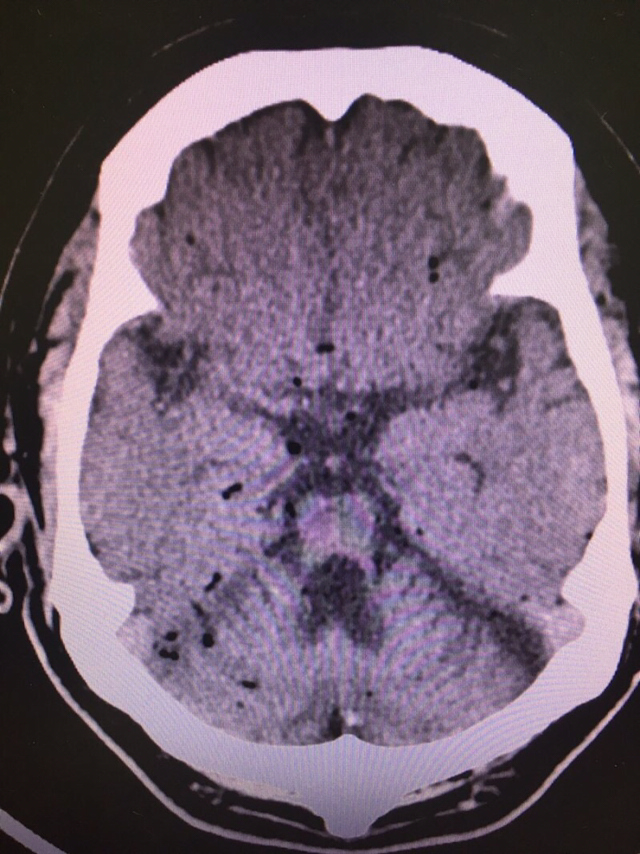

소뇌 위축증 앓았다는 60세 남성. CSI와 함께 응급실에 내원하였다. 엎드려 숨진 채 발견됐단다. 뇌출혈 여부 확인차 brain CT를 진행하였다.

출혈은 없으나 뇌에 구멍이 송송 뚫렸다. 사후 부패 과정에서 생긴 흔적으로 추정된다. 공기색전증 가능성도 완전히 배제할 순 없지만 가능성은 떨어진다.